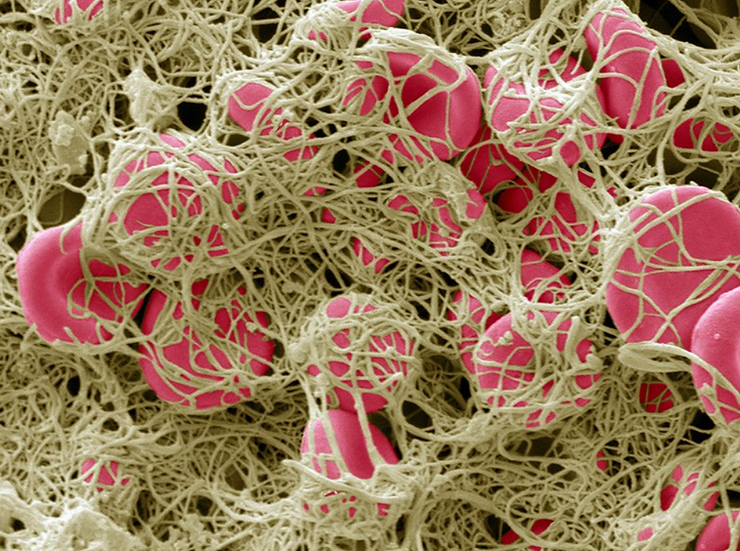

When red blood cells group or clot together into a fibrin net, a clotting protein created when there is injury to the cell membrane and/or endothelial cells that protect the lining of blood vessels, (See Picture 2) the red blood cells cannot enter into the pulmonary vein and then into the capillary pools to release their acidic carbon dioxide waste and pick up oxygen in the alveolus of the lungs. (See Illustration 1)[5]

Pathological blood coagulation or disseminated intravascular blood coagulation (DIC) inside the pulmonary vein will prevent the free passage of red blood cells into the alveoli of the lungs via the pulmonary capillaries. {See Phase Contrast Micrograph 3 and 4) Erythrocytes or red blood cells must go into the pulmonary capillaries single file. If they cannot pass into the pulmonary capillaries of the lung to the alveoli this will cause oxygen deprivation that leads to red blood cell hypoxia (carbon dioxide poisoning) degeneration, genetic mutation, sepsis and sudden death.[6][7][8]